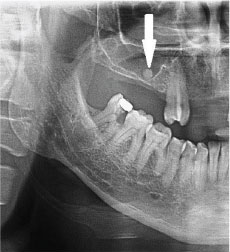

1. What condition can be seen in the following X ray? ( solid arrow)

the calcification within Stensen's duct of parotid